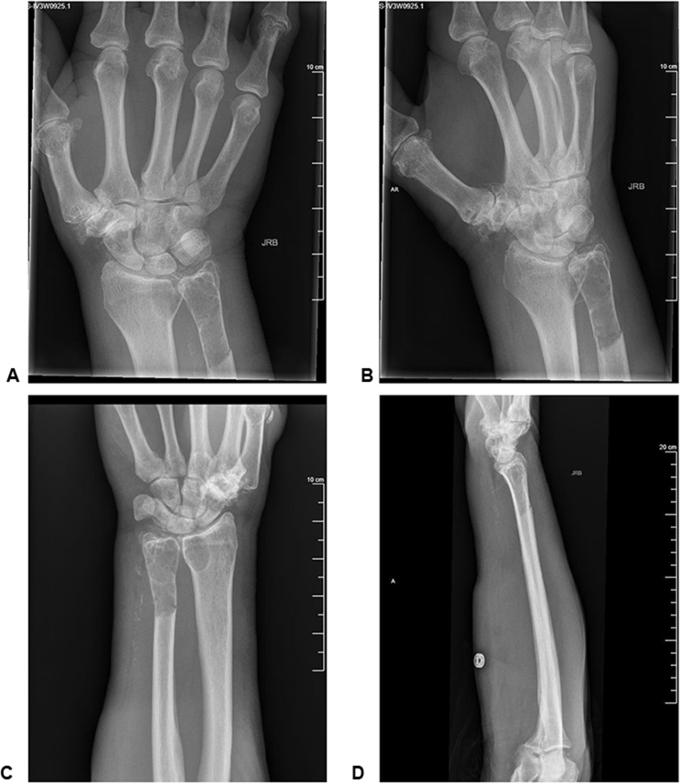

骨内肿瘤性二水焦磷酸钙晶体沉积病诱发的罕见病理性尺骨骨折

An Unusual Pathologic Ulna Fracture Induced by Intraosseous Tumoral Calcium Pyrophosphate Dihydrate Crystal Deposition Disease.

In this case report, we describe a novel occurrence of tumoral calcium pyrophosphate dihydrate crystal deposition disease (TCPPDCD) in a 76-year-old man that presented as an unusual, intraosseous, metadiaphyseal lesion of a long bone causing a pathologic fracture. A routine intralesional biopsy was performed, demonstrating granular deposits composed of polarizing, overlapping rhomboid crystals consistent with TCPPDCD. With limited numbers of reported cases of TCPPDCD, and the atypical intraosseous origin seen in this case, it is paramount to thoroughly evaluate all cases of TCPPDCD to clearly differentiate key findings that are essential in diagnosing and managing TCPPDCD.

在本病例报告中,我们描述了一名76岁男性发生的新型肿瘤性焦磷酸钙二水合物晶体沉积病(TCPPDCD),其表现为长骨骨干中段不寻常的骨内病变,导致病理性骨折。进行了常规的病变内活检,显示出由偏振、重叠的菱形晶体组成的颗粒状沉积物,与TCPPDCD一致。鉴于TCPPDCD的报告病例数量有限,且本病例中出现非典型的骨内起源,对所有TCPPDCD病例进行全面评估以明确区分诊断和管理TCPPDCD所需的关键发现至关重要。